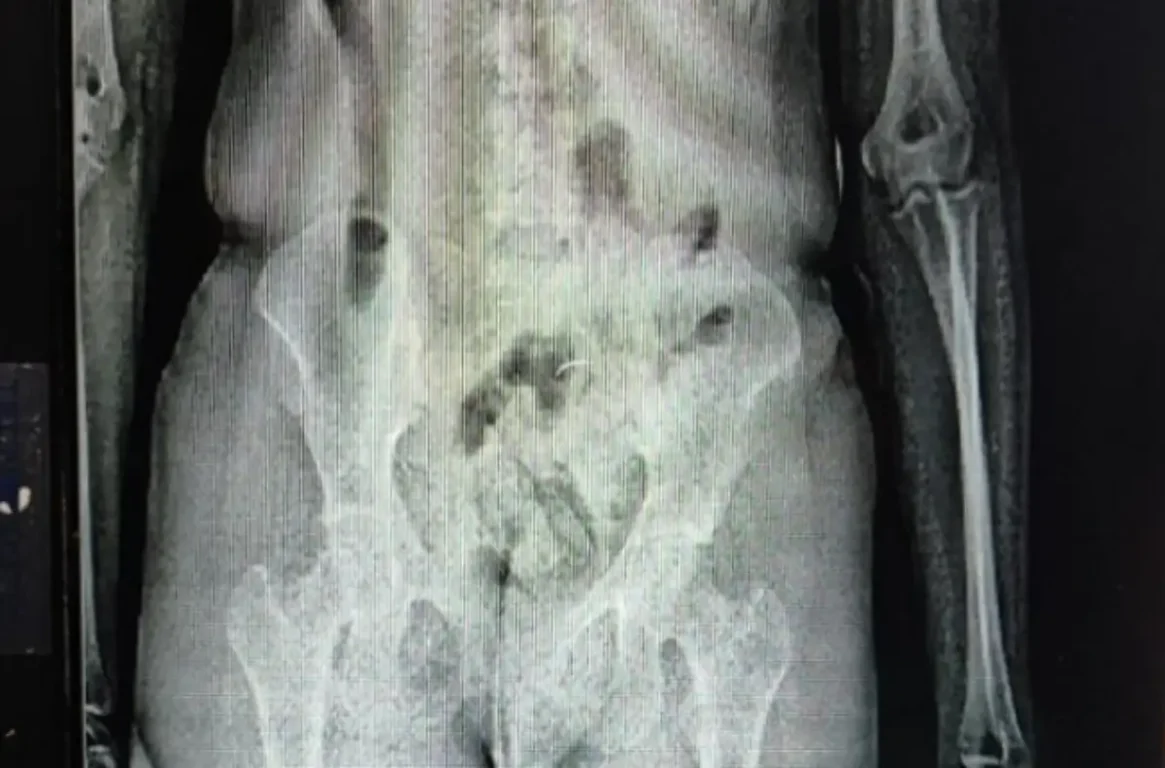

Ao passar pelo equipamento, policiais penais identificaram irregularidades na imagem corporal da visitante, companheira de um interno da unidade. As imagens apontaram a presença de um objeto em formato cilíndrico introduzido na cavidade pélvica.

Após a entrega espontânea do material, foi constatado que o objeto continha as substâncias ilícitas, acondicionadas em um único invólucro, envolto em fita preta. Segundo as informações, a aquisição da droga teria sido intermediada pelo custodiado, a quem o material seria entregue.